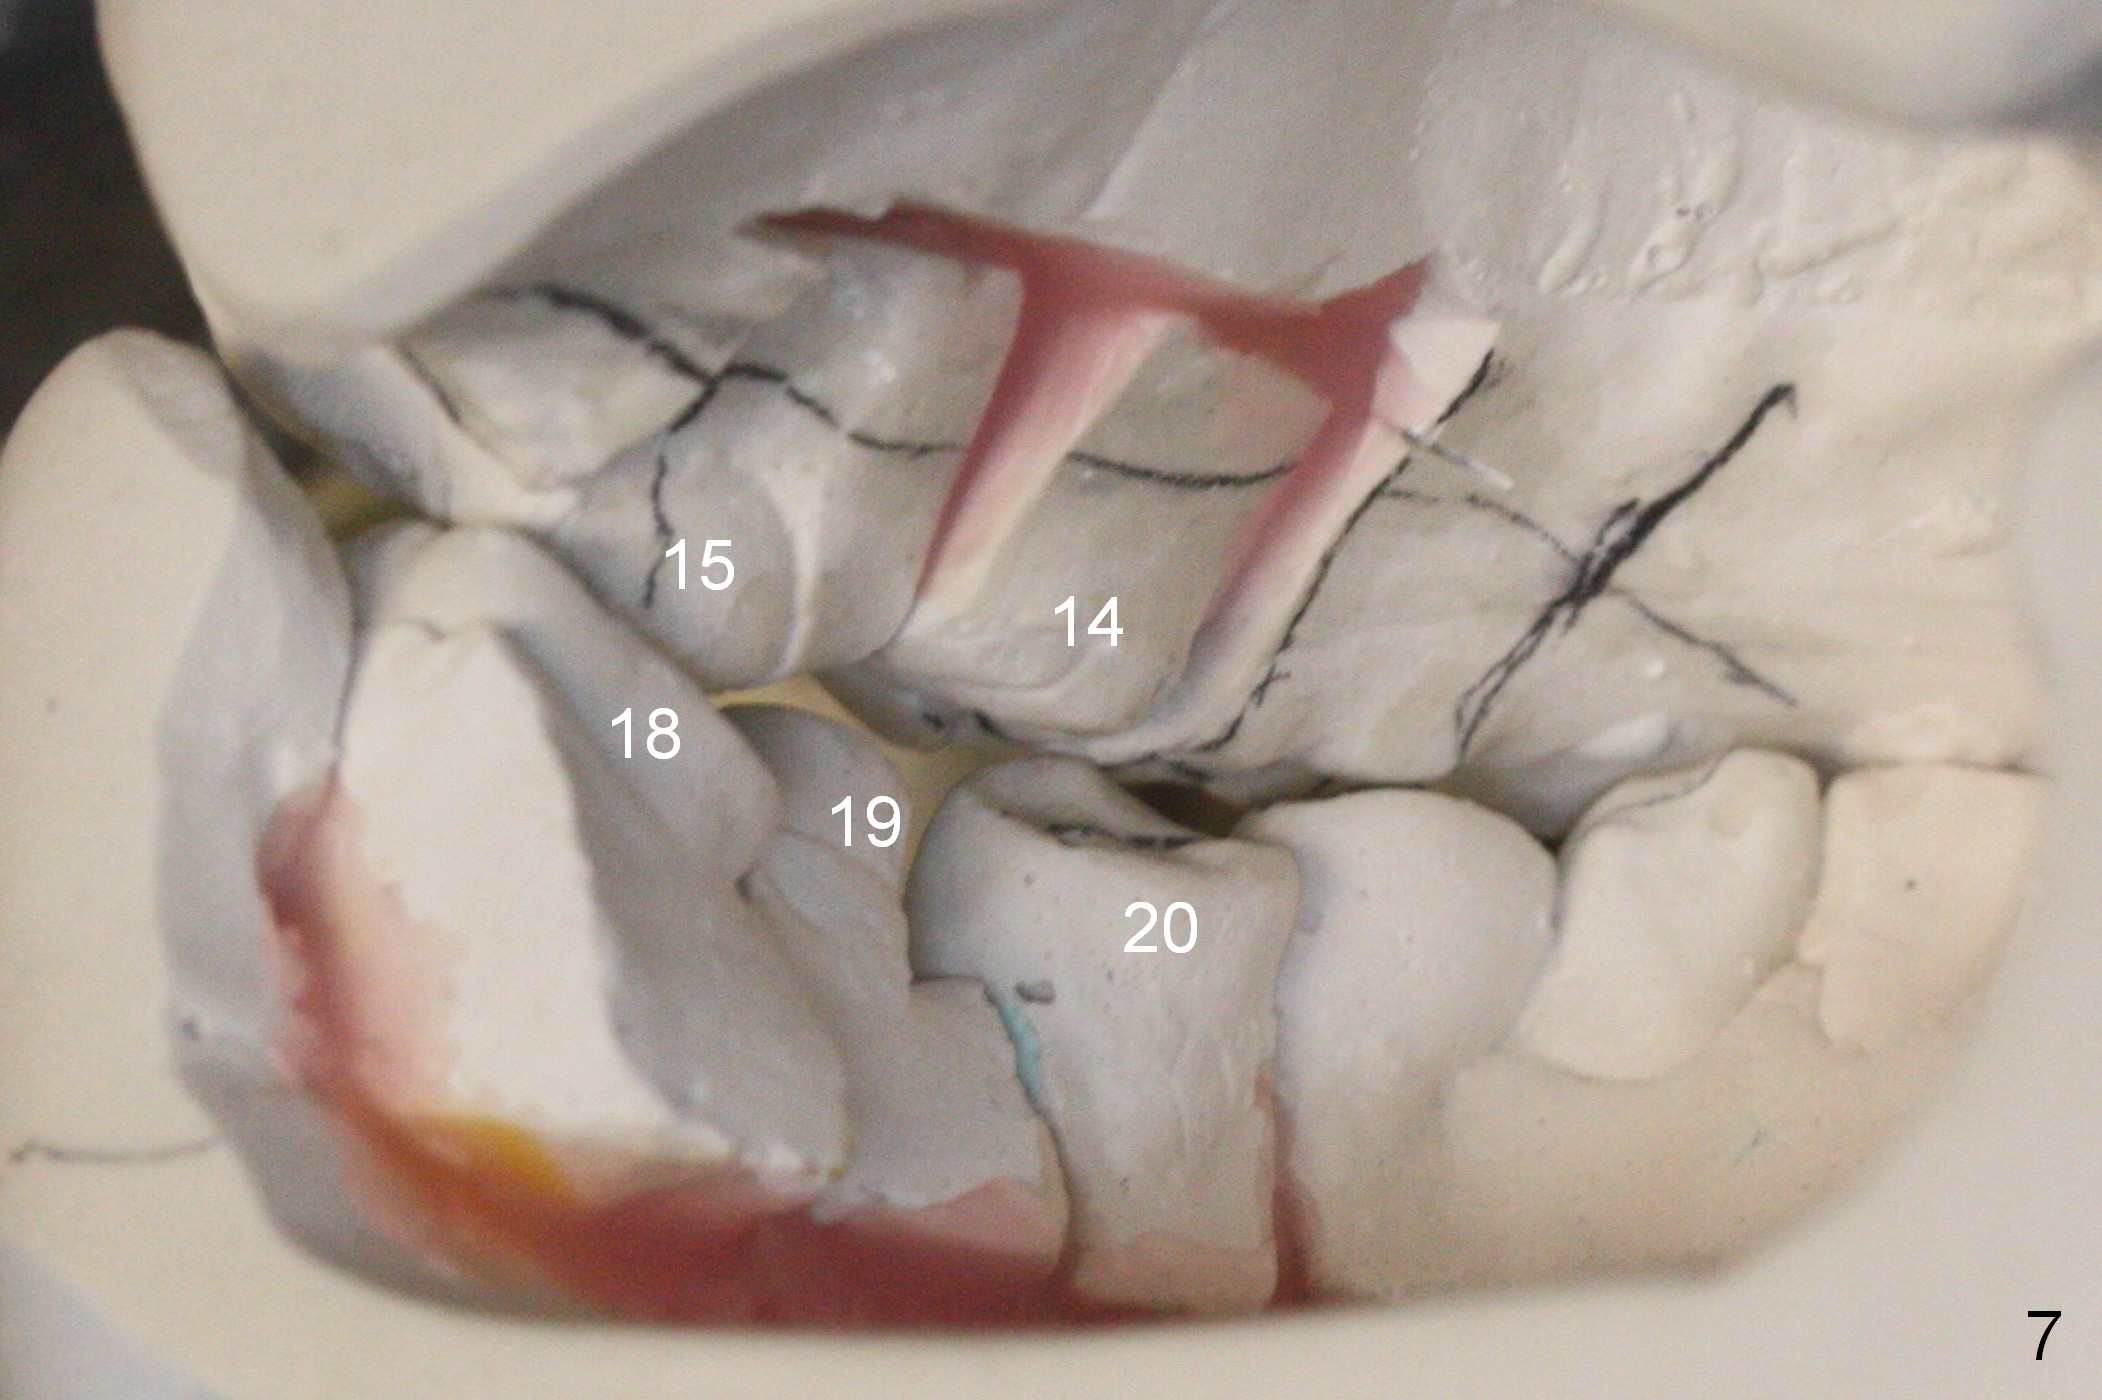

A 40-year-old man had automobile-related mandibular fracture and surgical reduction several years ago.  Since then there has been cross bite in the left molar region (Fig.1-2) with abnormal wear facets in the occlusal surface of the teeth #14, 15 and 18 (Fig.3,4 *).  At the time of implant placement at #19, the patient reports tooth sensitivity at #15 and wonders whether increase in the occlusal surface of the future crown at #19 can alleviate the tooth sensitivity or not.  In fact the tooth #14 and 19 were in cross bite when the sites of #20 and 21 were processed for implant crowns (Fig.1).  The cross bite of the left molar area appears to be so severe that surgical segmental osteotomy or orthodontic treatment is required (Fig.5-7).

In the lower arch, the buccal surface of the crowns at #20 and 21 is reduced substantially so that the crowns functions as lingual anchorage.  The abutment at #19 will be changed to an angled one; in the same way, the temporary crown at #19 is lingually positioned.  With full arch brackets and bands, the tooth #18 is expected to be lingualized (Fig.6 arrows).  Elastics can be placed between the left upper and lower molars (from upper lingual to lower buccal) to facilitate mutual shifting.